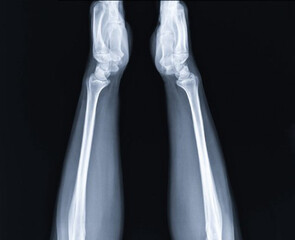

Podobny obraz Medical Elbow Anterior View X-Ray Radiograph Illustrating...